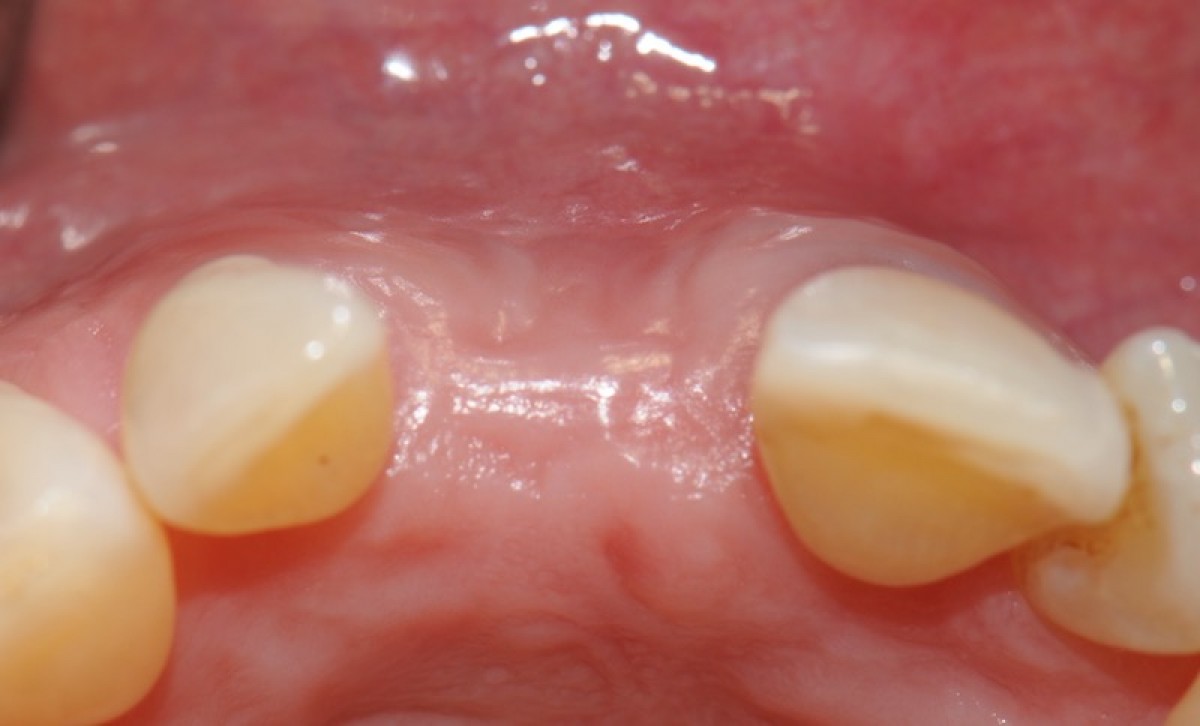

• soft tissue healing at 1, 4, 6, and 8 weeks from surgery (T1-4);

• 8 weeks after surgery, full wound closure was achieved in 9 out of 10 sites with healthy keratinized tissue;

• the histological evaluation of gingiva sample revealed the presence of healthy keratinized gingival tissue, with no signs of aberrations or anomalies;

• the mean colorimetric score ∆E between the regenerated site and the surrounding gingiva was 3.76 (3 to 6.55).

Seven out of 10 patients reported an excellent aesthetic integration of the matrix (∆E < 3.7).